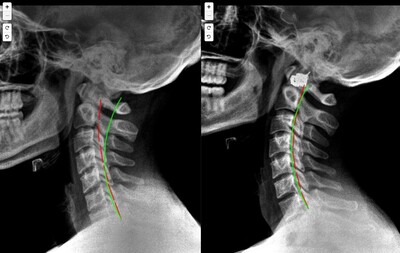

Results You Can See... and Feel!